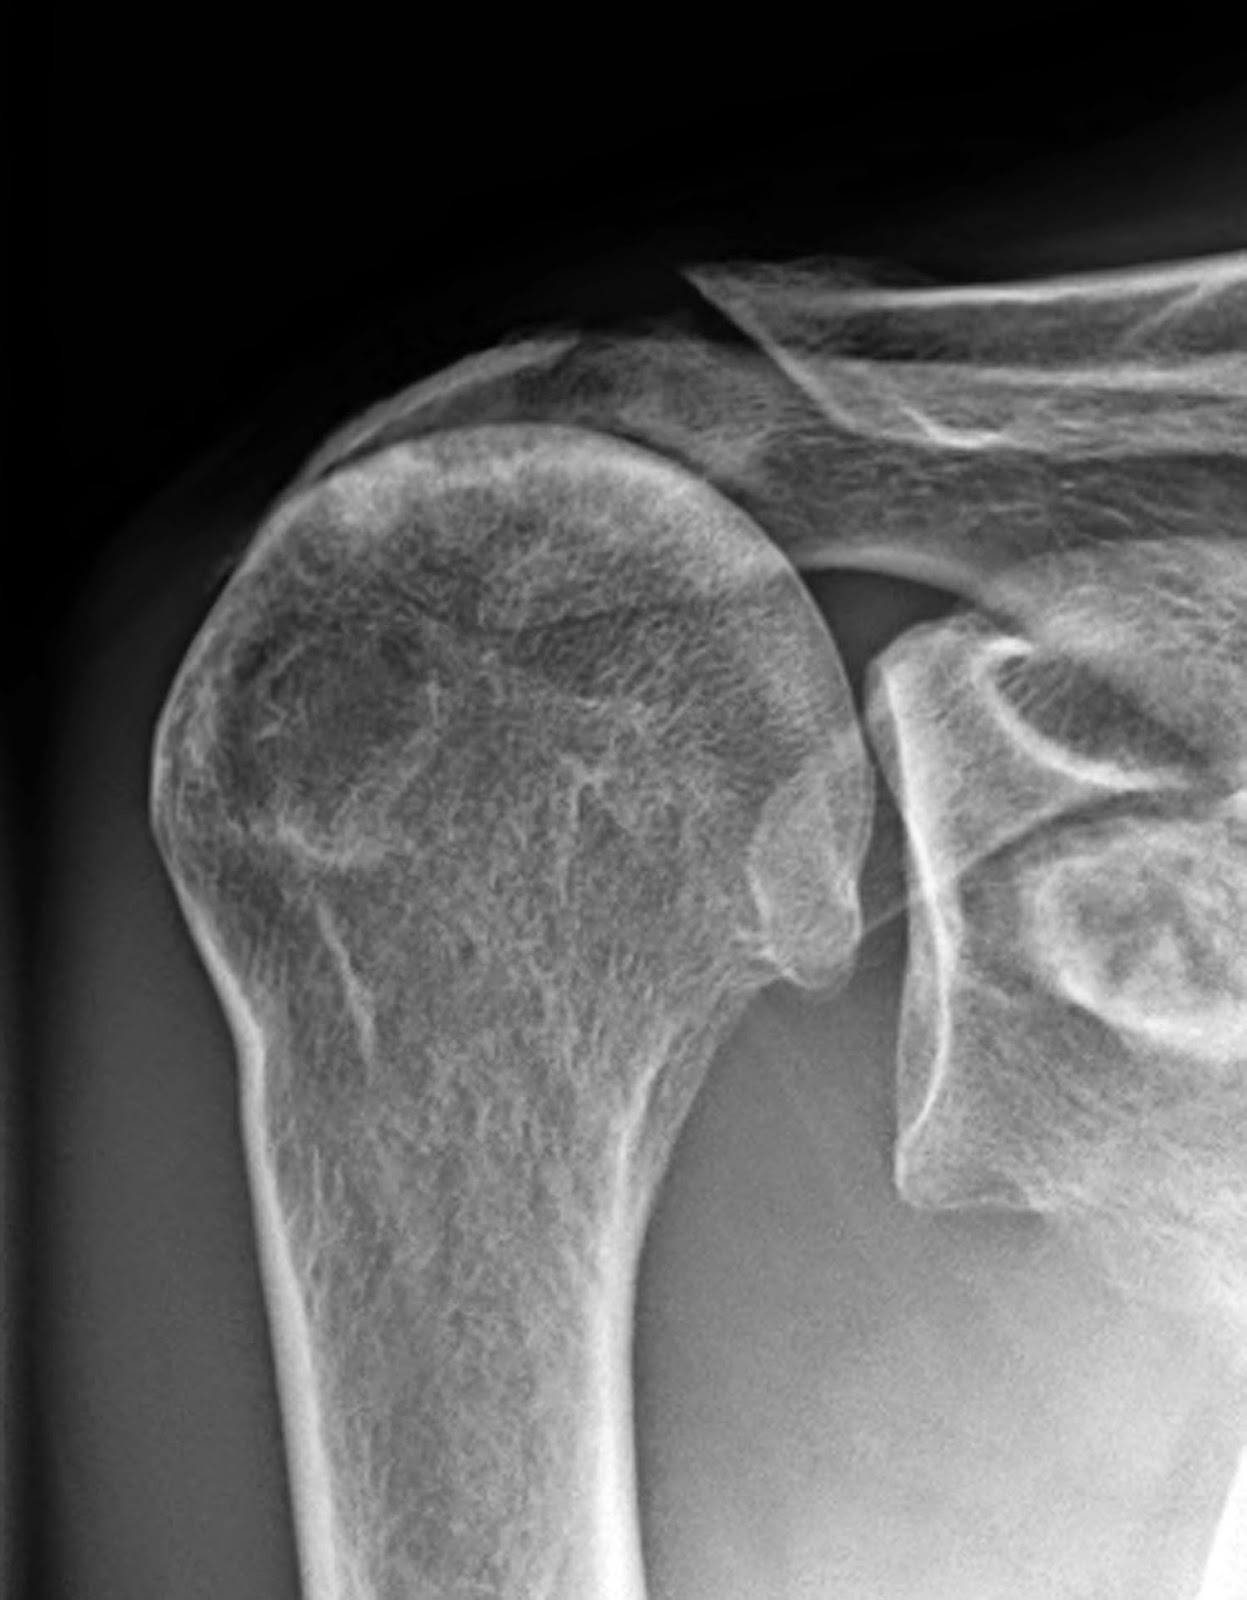

From www.bmj.com

Acute rotator cuff tears The BMJ Rotator Cuff Tear Degenerative  This review describes the epidemiology and natural history of degenerative. The mechanisms of rotator cuff tear (rct) healing, the intricate balance of collagen synthesis and degradation, and the influence of. An acute tear or a degenerative tear. The pathogenesis of these tears is still partly unknown. Rotator cuff tears are a very common source of. You can tear your rotator. Rotator Cuff Tear Degenerative.